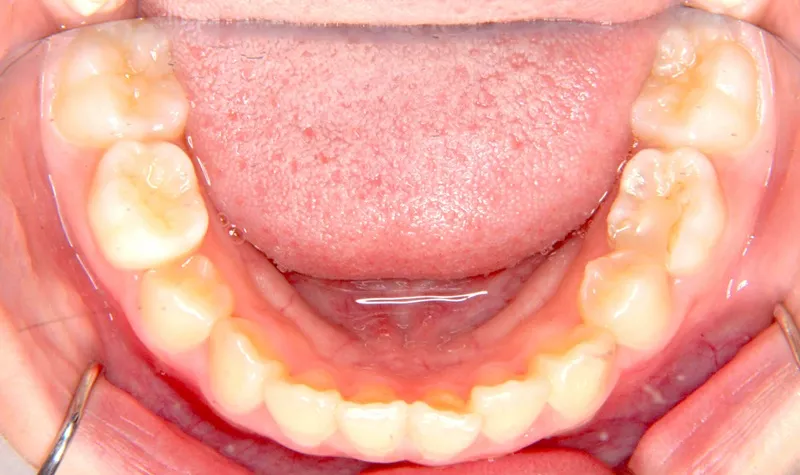

治療終了後

乳歯があるうちは上下オリジナル固定装置を利用し、永久歯が生えそろったらマルチブラケット装置を利用して治療しました。

治療回数35回、5年9ヶ月の治療期間で矯正治療を終了しました。